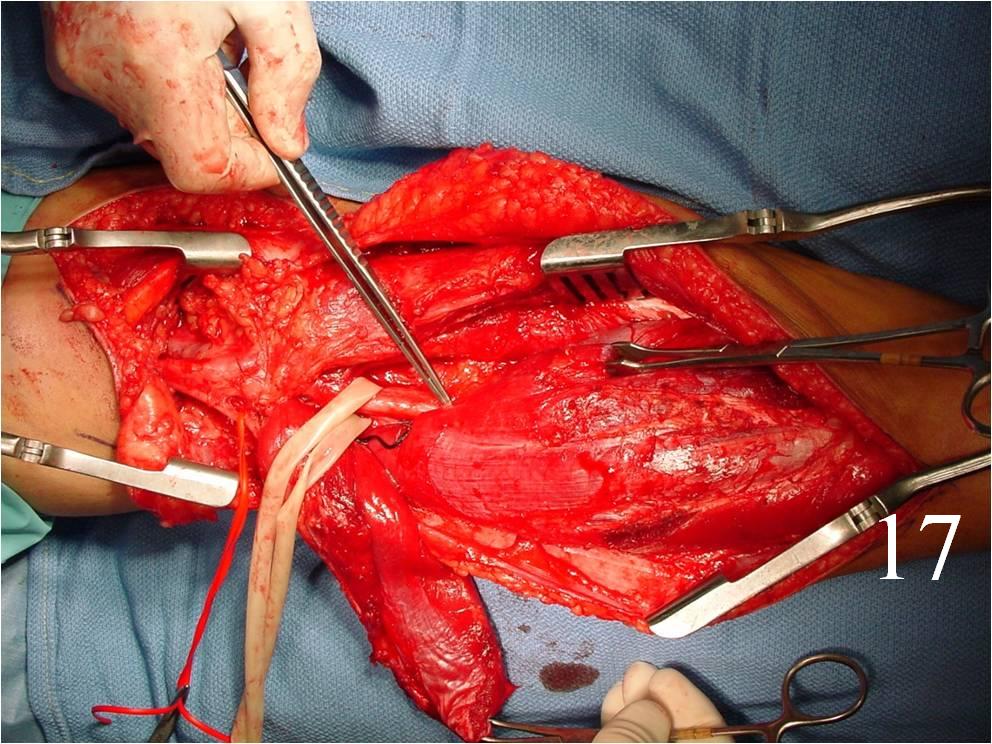

- Surgery: wide resection, chemotherapy, and possible radiation (Fig. 16-19)

Fig. 16-18: Intraoperative photograph shows a big rhabdomyosarcoma in the left calf. Photograph of a radical resection (Fig. 17) of the rhabdomyosarcoma to the calf. After the resection of the tumor (Fig. 18), multiple rotational flaps are performed to fill the dead space,